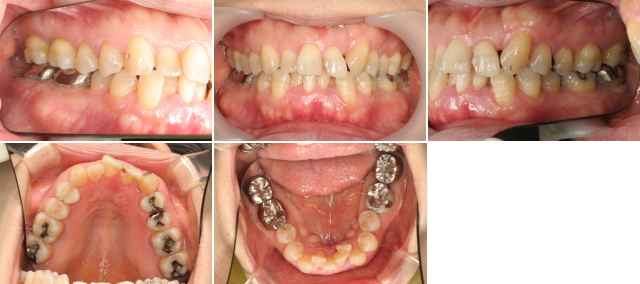

初診時の口腔内です。プラークコントロールはしっかりされています。歯肉には腫れや病的な赤みもありません。左上の小さい前歯が無く、犬歯が大きな前歯のとなりに移動してきています。